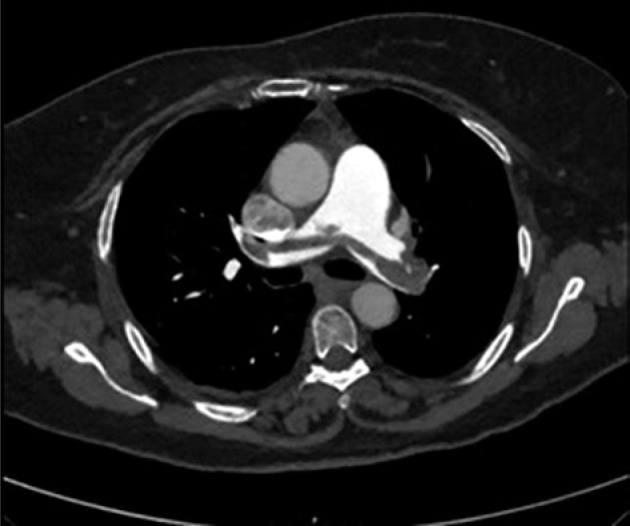

Case presentation: This case series reported three women, who experienced near-fatal saddle pulmonary embolisms shortly after undergoing high-dose-rate brachytherapy for locally advanced cervical cancer. In one patient, pulmonary saddle embolism led to hypovolemic shock due to intra-abdominal hemorrhage post-resuscitation, necessitating emergency decompressive laparotomy. Another case was complicated by neurological symptoms consistent with a stuttering stroke, following mechanical pulmonary thrombectomy.